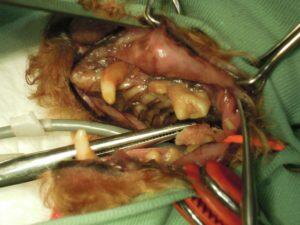

1.右側外観です。所々すでに歯がありません。

2.左側外観です。上顎犬歯の歯肉がかなり後退しています。

6.歯周病のため右側上顎の歯を全て抜歯し、

7.右側下顎の歯も骨折に注意して抜歯し、

8.左側上顎の歯も全て抜歯し、

9.左側下顎も全て抜歯しました。